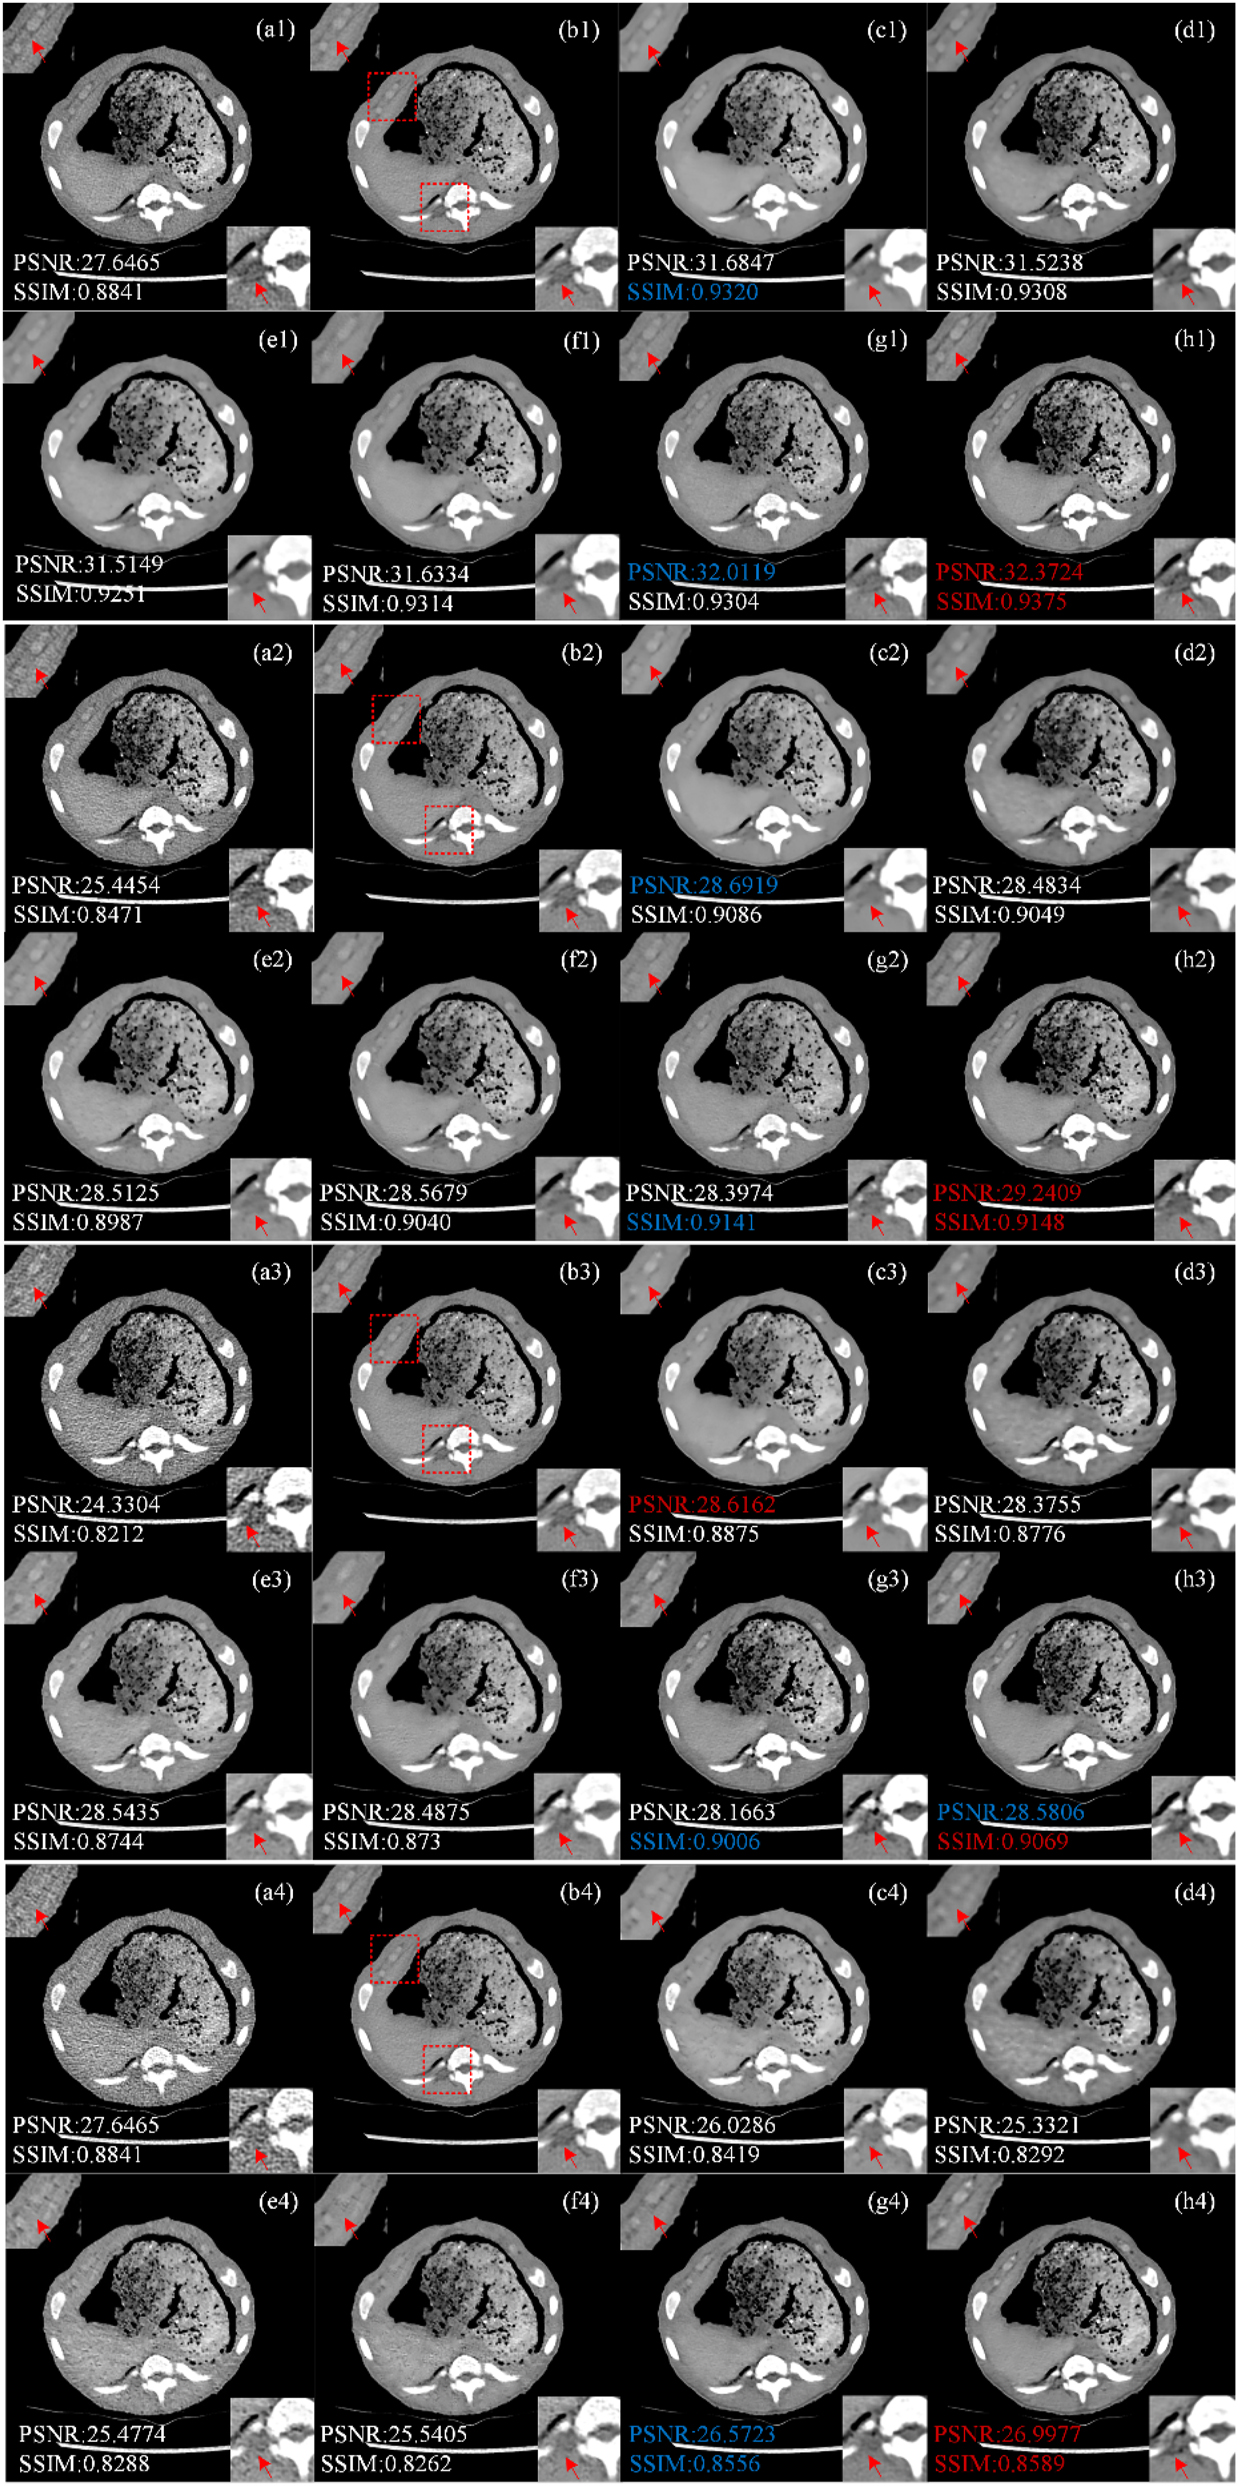

Piglet dataset visual assessment

Figure 5 shows the treatment results of representative piglet slices (Case 3) by different methods at different doses (50 %, 25 %, 10 %, 5 %). All CT images are displayed in window [−160, 240] HU. Figure 5(a1)–(a4) shows LDCT images at 150 mAs, 75 mAs, 30 mAs and 15 mAs. Figure 5(b1)–(b4) shows the corresponding NDCT images. Six comparison algorithms RED-CNN, Q-AE, EDCNN, CTformer, CoreDiff and CECDM. Comparing LDCT and NDCT images, it is found that the lower the X-ray dose, the richer the noise information in LDCT images. When the tube current drops to 15 mAs, the quality of LDCT image is significantly lower than that of NDCT image, and it is difficult to observe the tissue structure and detailed information.

Image comparison of different processing methods in piglet dataset. (a1–a4) LDCT (the tube currents are in order 150 mAs, 75 mAs, 30 mAs and 15 mAs), (b1–b4) NDCT, (c1–c4) REDCNN, (d1–d4) QAE, (e1–e4) EDCNN, (f1–f4) CTformer, (g1–g4) CoreDiff, (h1–h4) CECDM.

We zoom two ROI areas (marked by red rectangles in Figure 5(b)) for better comparison, trained and tested the four doses of LDCT separately, and we can see that above methods have different performance in noise reduction effect when tested on 150 mAs and 75 mAs datasets. Similar to the results from the Mayo dataset, RED-CNN, EDCNN, CTformer, and Q-AE were effective in suppressing noise at high doses (i.e. 50 % and 25 %). However, the RED-CNN image is too smooth (ROI regions (c1), (c2) in the lower right corner of Figure 5). Although EDCNN can retain edge information and has good noise reduction effect, there is still a problem of blurred details in the image (as shown in Figure 5(e1)–(e2)). CTformer can obtain improved images of better quality, but there is a smoothing phenomenon (as shown in Figure 5(f1)–(f2) top left corner ROI regions). The results of CoreDiff and CECDM are superior to those of the above methods, and it can be seen that the method proposed in this paper has good performance in both ROI regions (Figure 5(h1)–(h2)). However, when the tube current is reduced to 30 mAs and 15 mAs respectively, the image quality is seriously polluted. The two diffusion model-based methods proposed by us, CECDM and CoreDiff, have remarkable denoising effects and are obviously superior to other methods.

Piglet dataset quantitative assessment

Figure 5 shows the PSNR and SSIM indicators for the optimal and sub-optimal values of different noise levels, denoted in red and blue respectively. As can be seen from Figure 5, the X-ray dose is closely related to the LDCT reduction results of the six algorithms on the piglet test set. The higher the X-ray dose, the better the image index, and the lower the dose, the worse the image index.

It can be seen that when the tube current is 150 mAs and 75 mAs the indexes of RED-CNN are improved, and the optimal and sub-optimal values are obtained in some indexes. However, the index gap of other methods is not obvious. When the tube currents are 30 mAs and 15 mAs, CoreDiff and CECDM methods based on cold diffusion are obviously better than other methods, and most of the indexes are optimal. In general, the CECDM method proposed in this paper has achieved good results on measurements of LDCT image denoising at different doses, and has strong robustness.